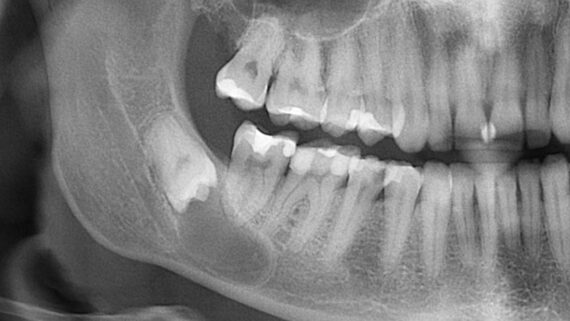

В боковом сегменте зубного ряда лучше просто оставить лунку заживать так, как есть:

и все нормально заживет. Через 1.5-2 месяца вы получите нормальные условия для имплантации: